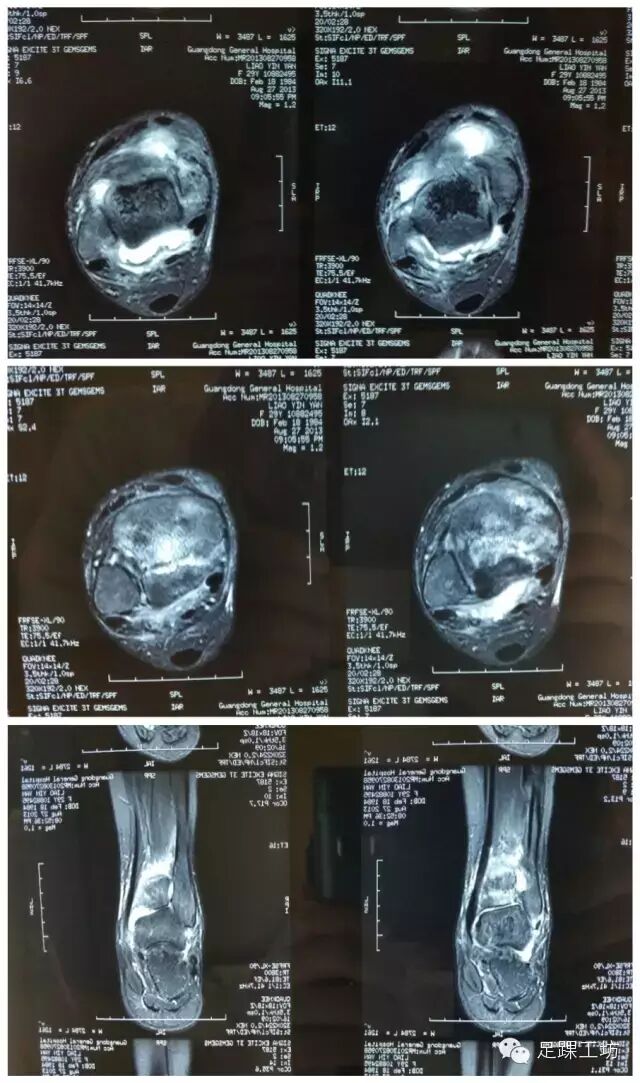

MRI